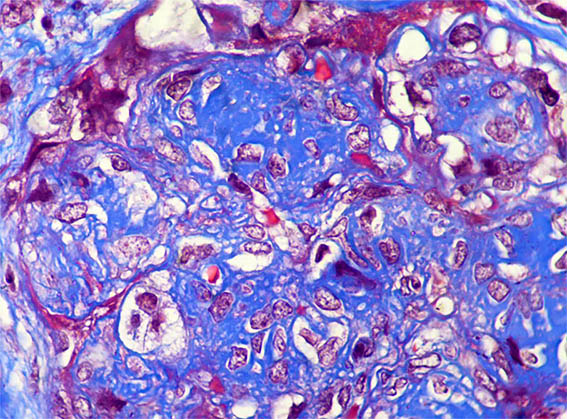

Figure 5. Masson's trichrome stain, X400.

Figure 6. Masson's trichrome stain, X400.